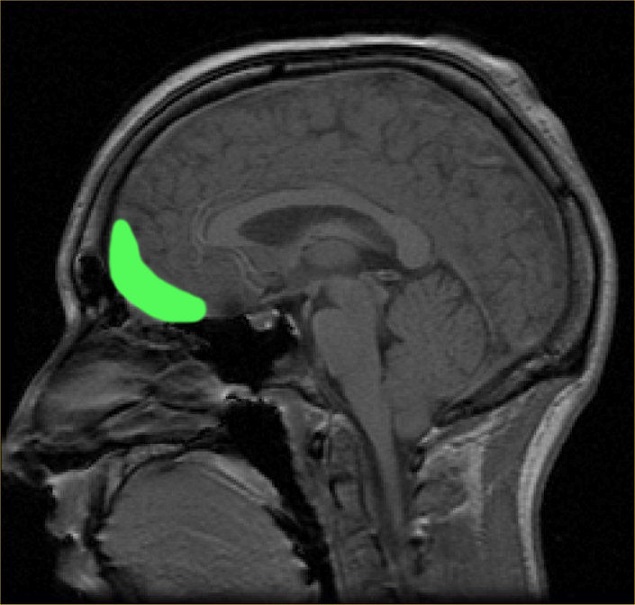

脑部的核磁共振扫描(不是来自这项研究)。

人类中间(与奖赏有关,OFC13)和侧面(与奖赏无关,OFC47/12)眼窝前额脑皮层网络,显示在忧郁症病患不同的功能连接。University of Warwick

这个成像技术能够显示出人类脑部受到忧郁症影响不同区块之间连接的活动,那就是中间和侧面眼窝前额脑皮层。侧面眼窝前额脑皮层与没有奖赏有关联,在忧郁症群的病患中,显示出相当强烈的连接。

如同研究小组所提,侧面眼窝前额脑皮层也和与自我感觉有关联的区块相连接。在那些受苦于忧郁症的人,这两个区块被发现有强烈的连接,或许解释了为什么有忧郁症的人经常有个人损失和自尊心低落的想法。